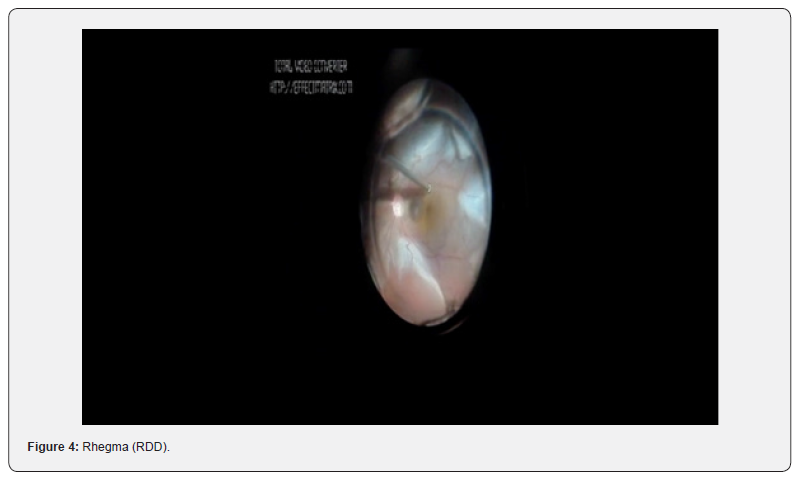

The patient was diagnosed with a pupillary block. Patient was started on triple topical therapy and oral acetazolamide. YAG-LASER iridotomies were performed. Patient persisted with ocular pain, flat anterior chamber and IOP on 36 mmHg regardless the patent iridotomies (Figure 3). Ultrasound bio microscopy (UBM) showed a flat anterior chamber due to irido-corneal contact and an anterior lens displacement. Malignant glaucoma diagnosis was then integrated, and the patient underwent Phaco-vitrectomy. Surprisingly, the surgery demonstrated a large retinal detachment with a localized rhegma (RDD) (Figure 4). Postoperatively VA remained on Hand movement, IOP on 16 mmHg with topical timolol, attached retina with optic nerve excavation 9.5/10 (Figures 5 &6).